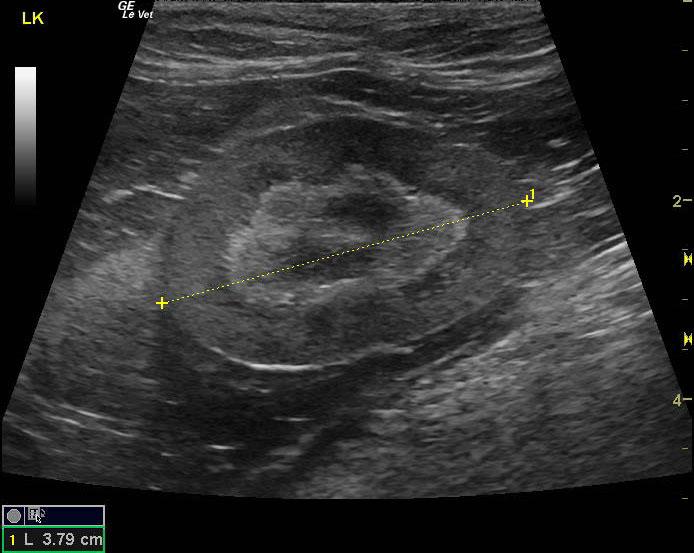

A 16-year-old spayed female cat was presented for evaluation of hematuria and inappropriate urination. On urinalysis, an inappropriate specific gravity (1.014) and hematuria were evident. The only abnormality on blood work was mild anemia.

A 16-year-old spayed female cat was presented for evaluation of hematuria and inappropriate urination. On urinalysis, an inappropriate specific gravity (1.014) and hematuria were evident. The only abnormality on blood work was mild anemia.